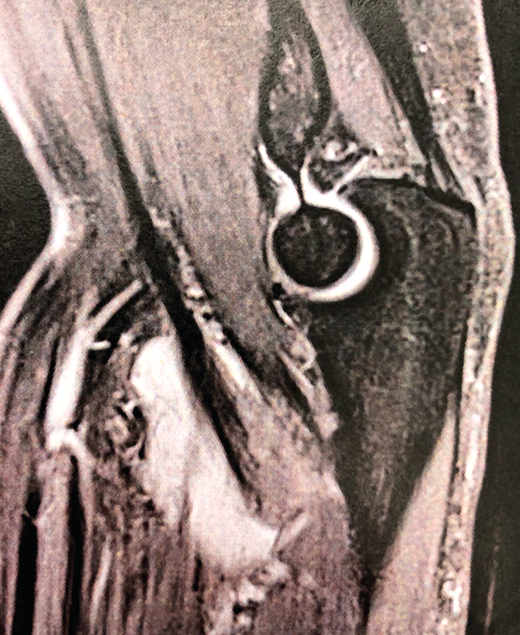

Figura 1. Corte sagital de resonancia nuclear magnética con bursitis bicipitorradial.

Las lesiones del bíceps distal representan un grupo variado de alteraciones que incluyen la bursitis bicipitorradial (Figura 1), la tendinosis, las roturas parciales y las roturas completas. Es probable que las roturas completas representen el estadio final de la tendinopatía en la mayoría de los casos(1). Son relativamente frecuentes en pacientes varones de mediana edad durante la práctica deportiva y en el medio laboral. El diagnóstico es eminentemente clínico, pero apoyado en pruebas de imagen como la ecografía y la resonancia nuclear magnética (RNM). En los últimos años, el número de lesiones del bíceps distal diagnosticadas ha aumentado debido a la mejoría de las pruebas diagnósticas y su mejor comprensión(2) y, aun así, las roturas parciales son frecuentemente infradiagnosticadas. En general, se recomienda tratamiento conservador para las bursitis bicipitorradiales y para las tendinosis. En cuanto a las roturas parciales de bajo grado, la mayoría de los expertos recomiendan también tratamiento conservador, consistente en modificación de la actividad previa, uso de antiinflamatorios no esteroideos (AINE) y rehabilitación, aunque no está clara la duración concreta de dicho tratamiento antes de decidir un tratamiento quirúrgico. La cirugía queda destinada a las roturas parciales sintomáticas transcurridos entre 3 y 6 meses de tratamiento conservador correcto, roturas parciales de alto grado y roturas de espesor completo, con el objetivo de recuperar fuerza de supinación y de flexión(3,4). El objetivo de este artículo es presentar las distintas lesiones del bíceps distal, los métodos diagnósticos más adecuados y las alternativas terapéuticas para cada una de las entidades patológicas.